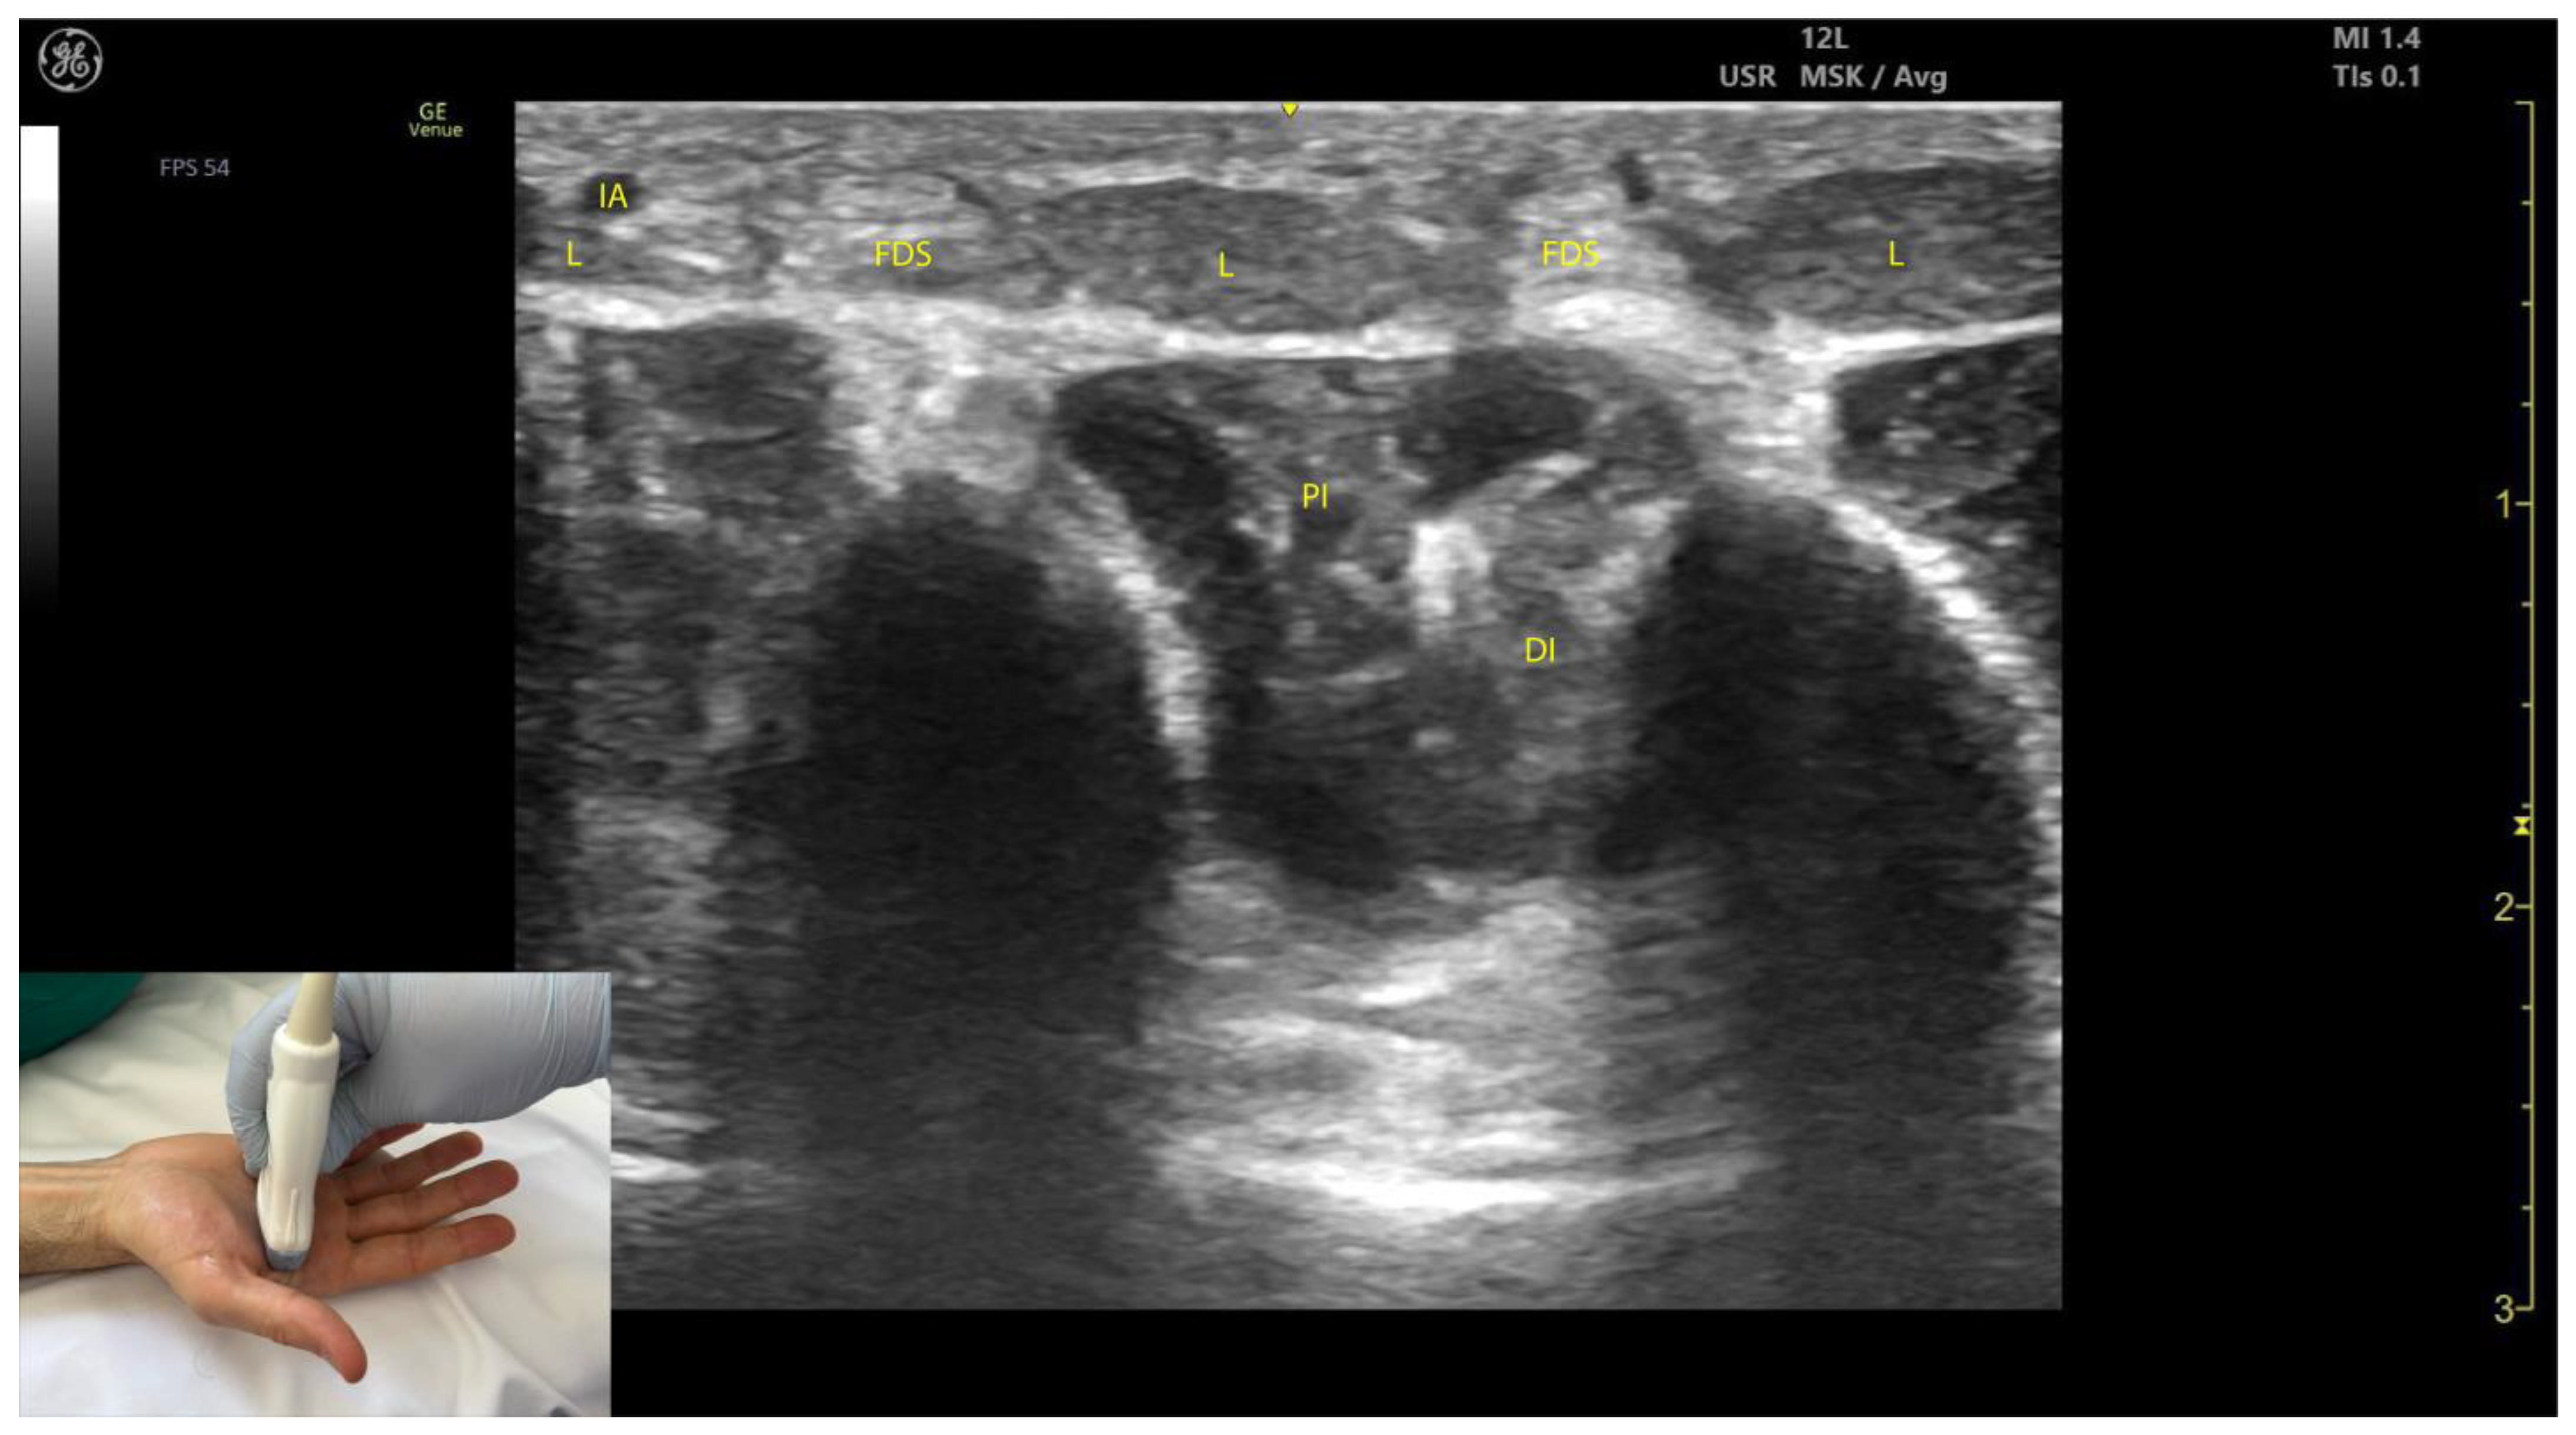

2.12.3. Key Ultrasound Landmarks [63,64,65,66] (Figure 12)

- Muscle morphology: Lumbricals L1 and L2 are unipennate, while L3 and L4 are bipennate. Intramuscular fascia corresponding to L1 and L2 can be visualized.

- Innervation and vascular supply: Superficial to L1 and L2 are branches of the median nerve, while superficial to L3 and L4 are branches of the ulnar nerve, each accompanied by arterial branches from the dorsal carpal arch.

- External fascia: The lumbrical muscles lack a pronounced fascia to distinctly separate them from the FDS tendons (adjacent structures), which may pose challenges for precise localization during BoNT-A injections.

- Dynamic evaluation: Scanning distally toward the MCP joints reveals an increase in the size of L1–L4 and a corresponding decrease in the size of the AP. Placing the transducer at the midpoint of the metacarpals II–V and performing flexion and extension maneuvers of the fingers highlights the contraction of L1–L4 and the associated action on the tendons of FDS and FDP. The lumbricals appear as hypoechoic structures with hyperechoic speckles, described as a “starry sky” pattern, while the FDS and FDP tendons are hyperechoic with parallel fibrillar lines.

2.13.3. Key Ultrasound Landmarks [60,67,70] (Figure 13)

- Muscle position: The dorsal interossei are the most superficial muscle structures on the dorsal aspect of the hand.

- Muscle morphology: The dorsal interossei are bipennate muscles, whereas the palmar interossei are unipennate. Musculoskeletal ultrasound also allows visualization of the intramuscular fascia within these structures.

- External fascia: The interossei muscles lack a pronounced fascia to clearly demarcate the dorsal and palmar interossei (adjacent muscle masses), which can make precise localization during BoNT-A injections more challenging.

- Muscle size: The first dorsal interosseous muscle is larger compared to the other dorsal interossei. Deep to it lies the AP, which decreases in size as the first dorsal interosseous muscle increases during dynamic scanning cranially.